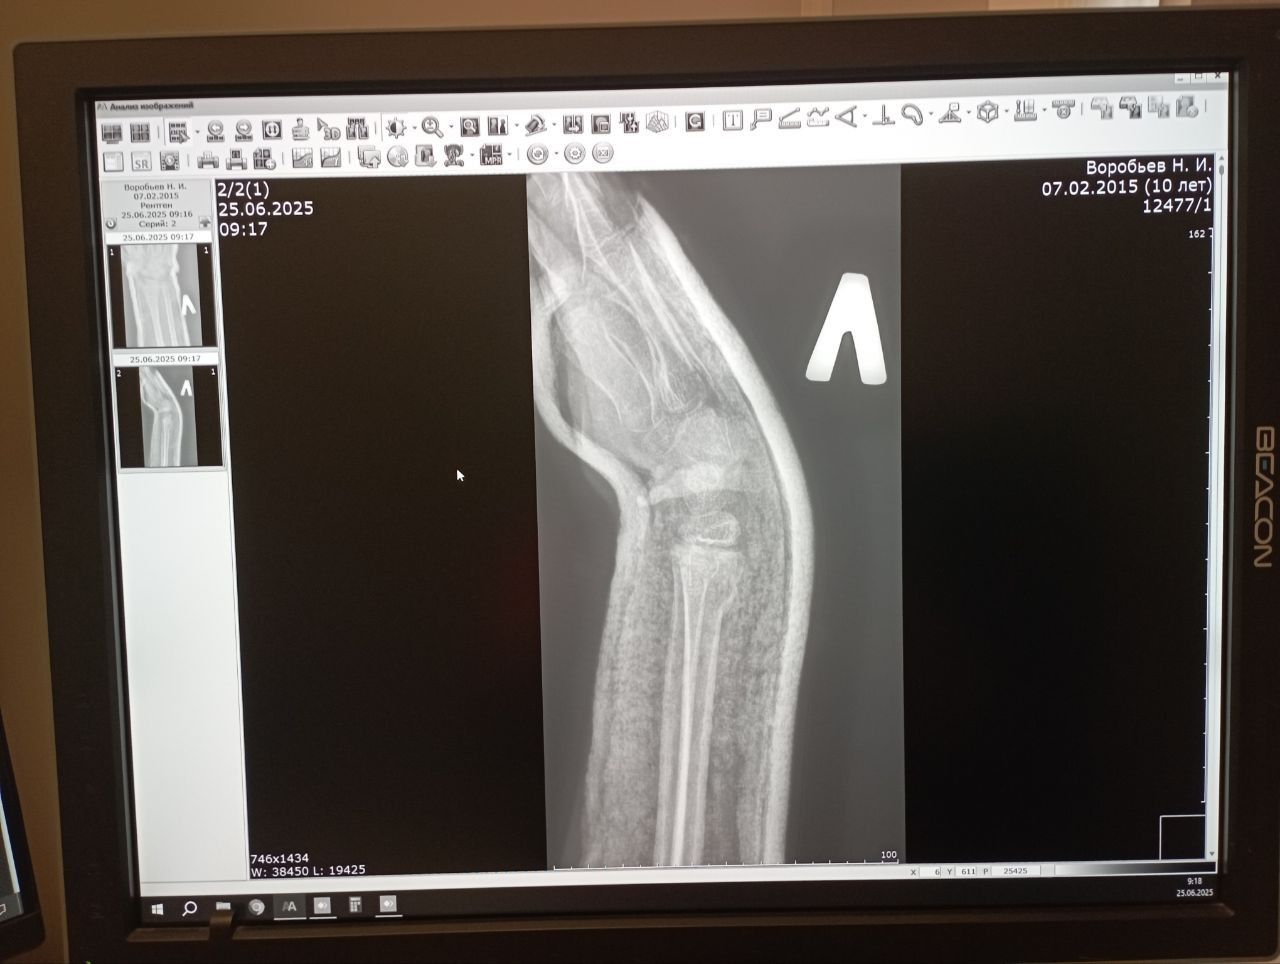

Сегодня был 7 день после травмы. Мы сделали снимок, можете просмотреть пожалуйста и прокомментировать. Спасибо

По новым снимкам видно, что положение костных отломков остаётся удовлетворительным, вторичного смещения нет. Контур перелома прослеживается, начальных признаков костной мозоли пока не видно (что нормально на 7 сутки). Гипс можно сохранять дальше, как минимум до 3-4 недель от момента травмы. Если самочувствие хорошее то лечение продолжается по плану.